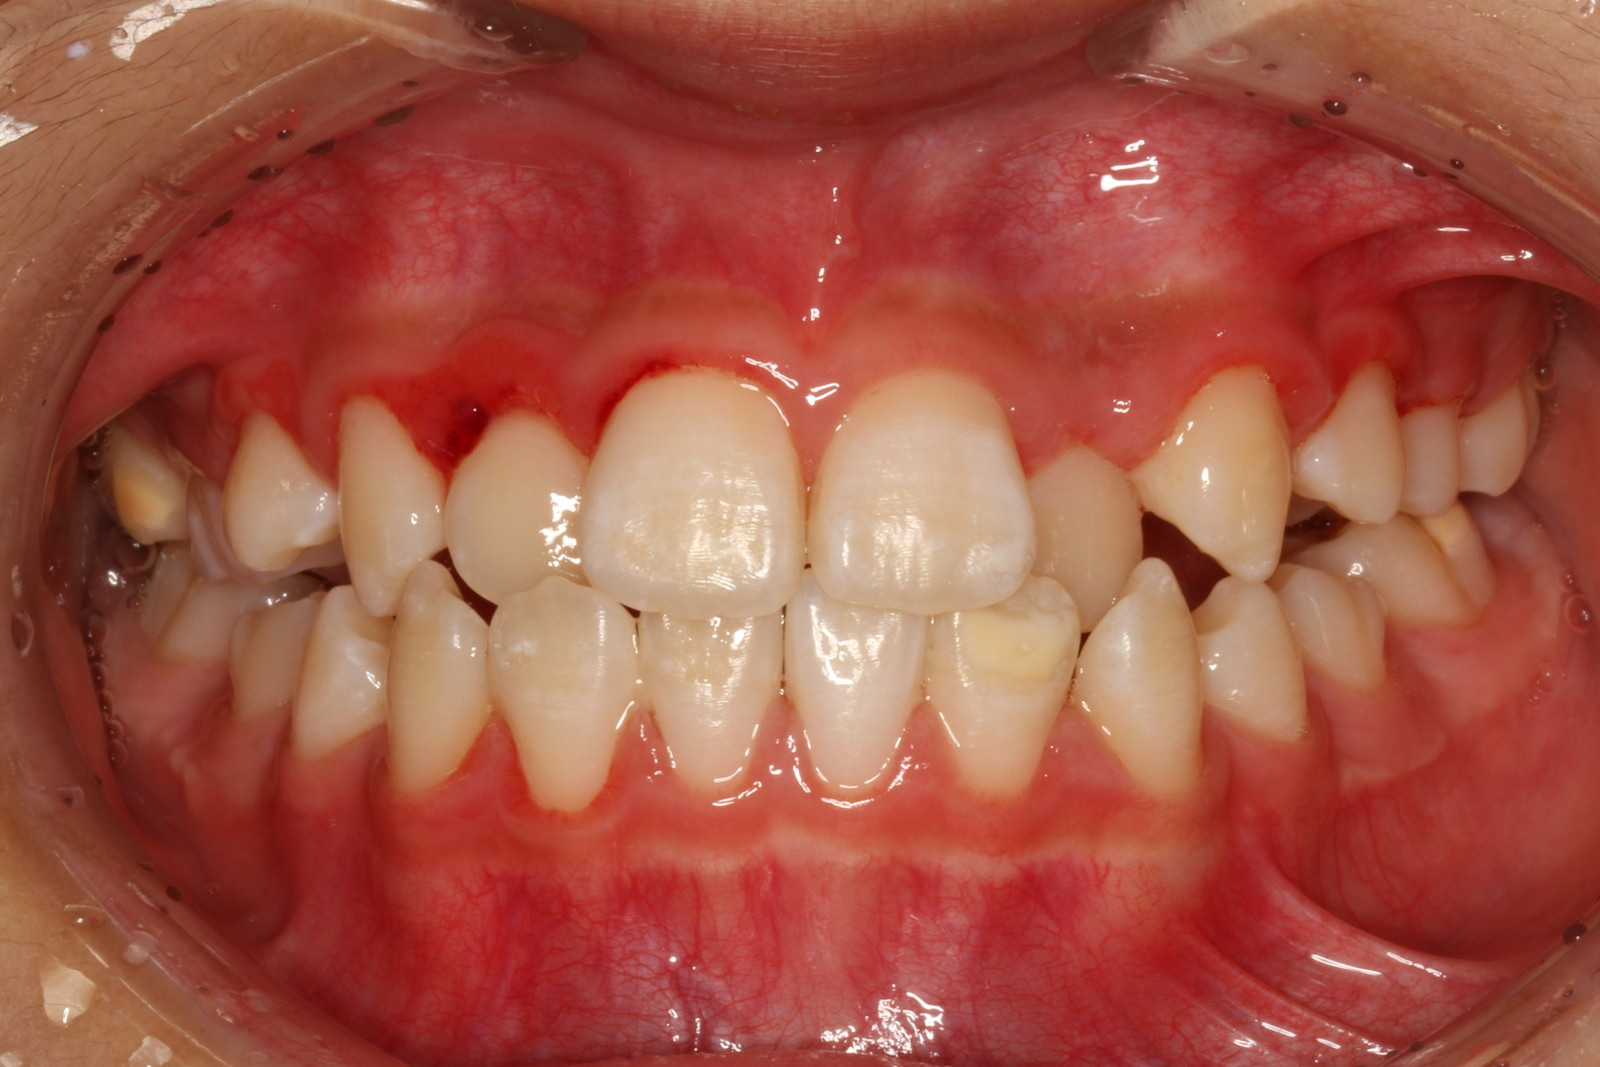

問診を行い、お口の悩みや希望を確認します。レントゲン撮影や口腔内写真の撮影など、必要に応じた精密検査を行います。